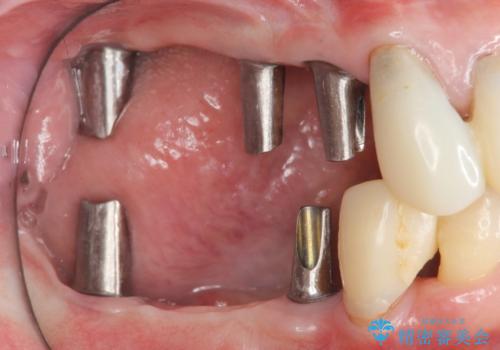

- 歯周病で失った奥歯や、グラグラしている歯の治療を希望され来院されました。

残すことのできない歯を抜去したのち、骨を造成し安定した環境下で長期的な予後を期待できるインプラント治療を計画します。

奥歯を多数失い全く噛めない期間があり、困り果てて来院されましたが、インプラント治療をおこなったことでしっかりと噛めることができるようになりまた食事を楽しめるようになったと大変喜んでいただくことができました。